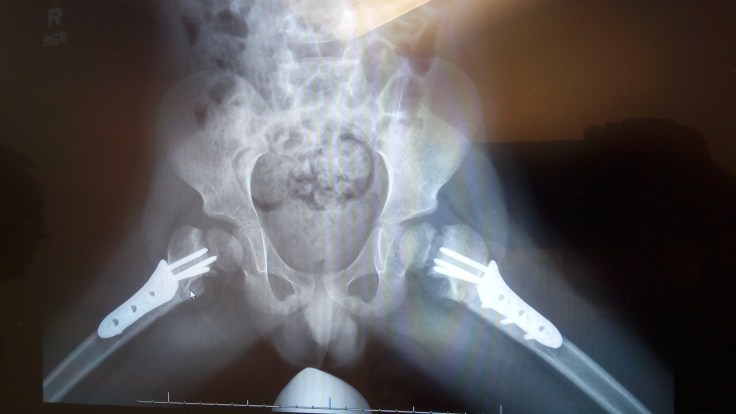

For some reason, nobody sent us to get any x-rays taken before we saw the doctor, and since she assumed we had taken x-rays she just pulled up the most recent ones in his file. Those x-rays, though, we’re from our last visit three weeks ago. Upon hearing that we hadn’t taken any x-rays yet, she immediately took us over to get them taken, and then we met back up with her a few minutes later. At that point she was very happy with the progress he had made. She said one hip is mostly healed, and the other is showing very good progress. This isn’t the best view for you to be able to see, but this is one of the x-rays they took today and you can see the plates really well as well as the angle that the hips fit into the socket.